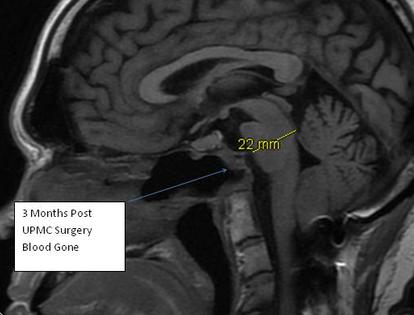

MRI 3 months post surgery -   Blood resolved. Brain stem relaxed and expanded forward by almost 4 mm which might as well be a football field (in places) in the brain for those who are not familiar with brain anatomy.

Physicians at UPMC in Pittsburgh developed new technique around 2010. Using a small endoscope, through the nose, then a small catheter through the back of the nasopharynx ( nose/mouth ) they removed ( via tiny drill ) most of C1 and C2. Quite risky being that close to brain stem. No small complications, sort of an all or nothing thing. This is me 2 weeks post surgery.